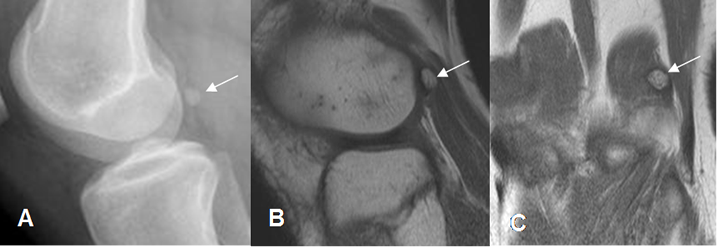

Fig 25. Fabela normal.

A: Rx lateral, B: RM sagital en T1 y C: RM coronal en T1. Fabela normal, en la parte posterior del cóndilo femoral externo.